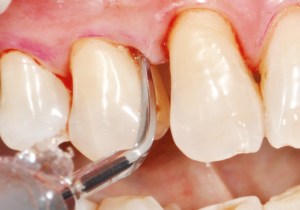

歯ぐきにニキビのような膿の袋 (フィステル or サイナストラクト) ができて気付くこともあります。

押すと膿が出たり少し痛みがありますが、強い痛みはほとんどありません。